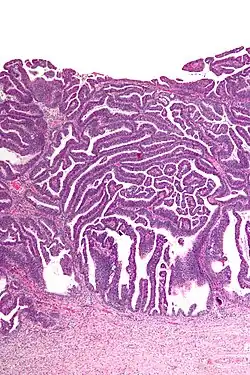

The name of the lesion describes it microscopic appearance. It has nipple-like structures with fibrovascular cores (papillae) that are long in relation to their width (villus-like), which are covered with a glandular pseudostratified columnar epithelium.

-

Very low magnification -

Intermediate magnification -

Very high magnification